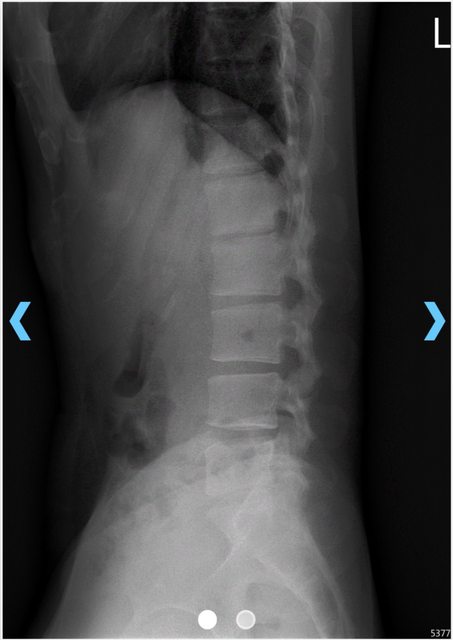

馬偕醫院拍的X光片 https://i.imgur.com/GEgkCA4.jpeg

juor2: 但你的X光我有講了就慢性退化的椎間盤突出跟我本人一樣 06/06 21:56

juor2: 但說實話你的X光用間接證據看,椎間盤突出或是退化是機率06/06 23:30

juor2: 很高,會建議先讓急性期下來。當時不確定你會想要自費作治 06/06 23:31